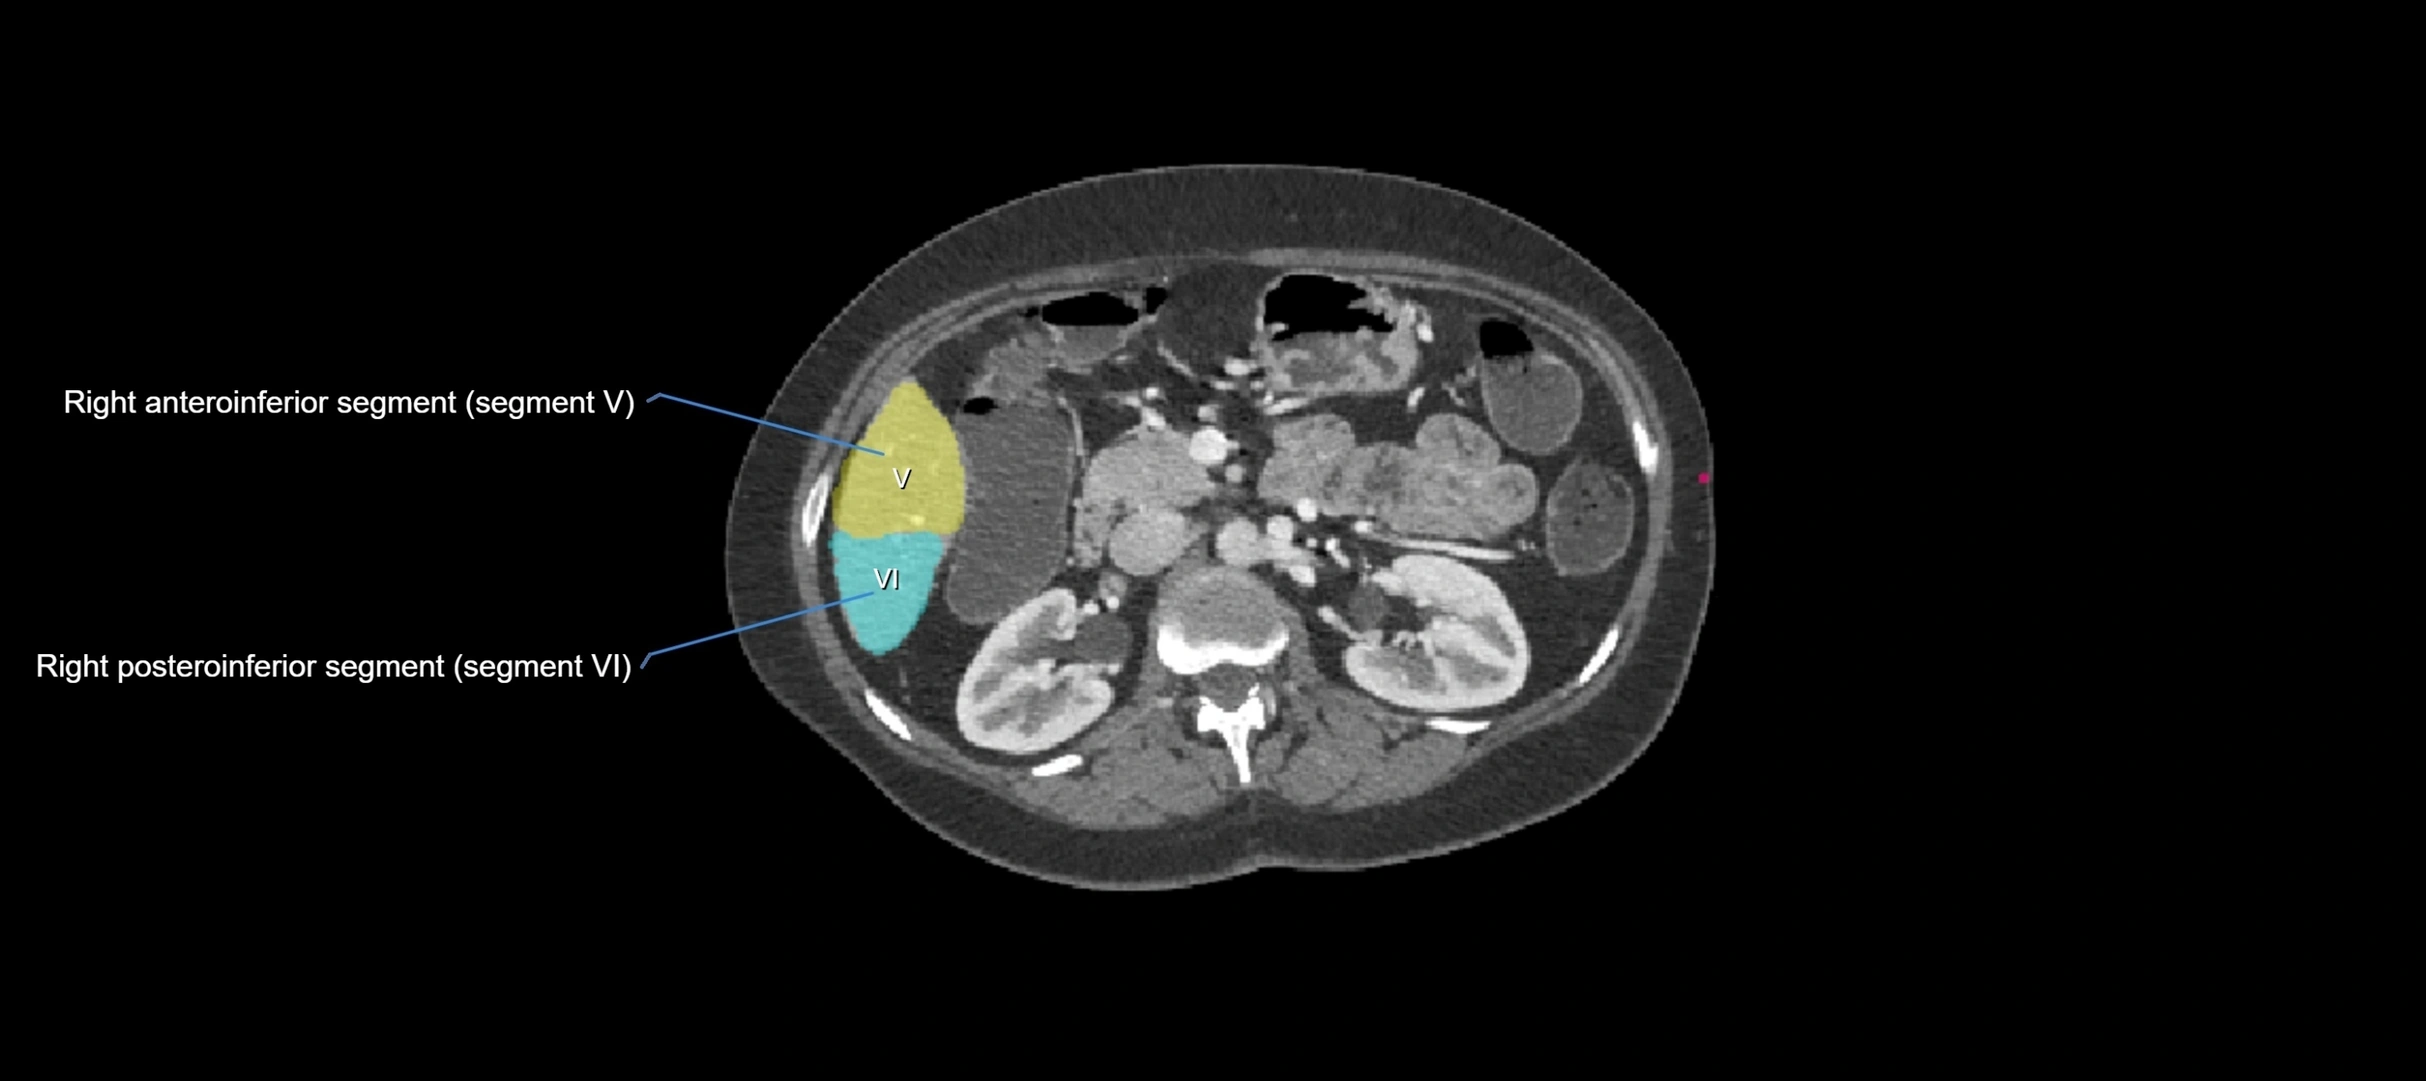

The caudate lobe of the liver is a distinct anatomical subdivision of the liver, designated as segment I in Couinaud’s classification. It lies on the posterior surface of the liver, between the fissure for the ligamentum venosum (left boundary) and the groove for the inferior vena cava (IVC) (right boundary). Superiorly, it is related to the posterior liver surface, and inferiorly it is separated from the left lobe by the porta hepatis.

• Segment I (Couinaud classification)

CT Appearance

CT Pre-Contrast:

• Caudate lobe appears as a soft-tissue density, isodense to the rest of the liver

• Enlargement may be appreciated in cirrhosis or Budd–Chiari syndrome